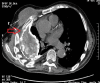

Empyema necessitans is a rare clinical finding nowadays. We report the case of a patient admitted in our ward for investigation of an unknown onset anterior chest wall mass, with no accompanying signs or symptoms. It is noteworthy that the patient had had pulmonary tuberculosis submitted to thoracoplasty more than 60 years before. Thoracic MRI showed a large heterogeneous mass, with a thick wall and internal septations located at the right anterior chest wall, as well as a heterogeneous content inside the right pleural cavity, with direct communication between both. An aspirative puncture of both masses was performed, with positive cultures for Mycobacterium tuberculosis, thus leading to the diagnosis of pleural tuberculosis with anterior chest wall empyema necessitans. A drain was inserted and antibiotics started. This case draws our attention to a very rare complication of pulmonary tuberculosis and its surgical treatment, though it aroused many decades after primary infection.